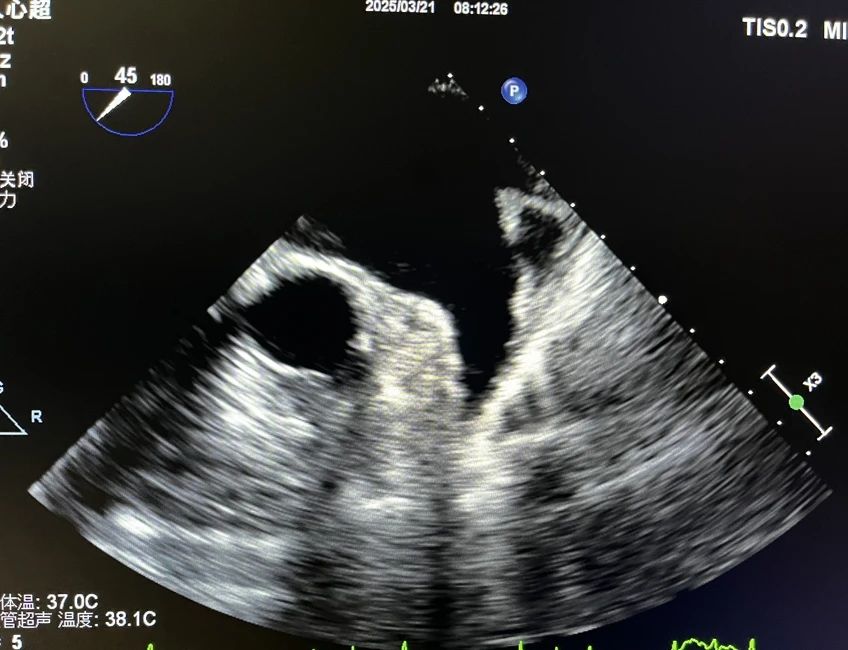

超声科团队在术前充分沟通后,通过先进设备及精准操作,成功获取左心房及肺静脉三维成像,排除了左心耳血栓风险,并精准定位肺静脉开口,为心血管内科团队开展手术提供了关键影像学依据,保障了手术顺利进行。术后,患者生命体征平稳,无相关并发症。

房颤,即心房颤动,是一种常见的心律失常,指心房失去规律的舒张和收缩,代之以无序的颤动,房颤有发生心功能减退、心源性栓塞等风险,且发生的脑栓塞通常致残率非常高。经导管射频消融术是持续性房颤的有效治疗手段,目前成功率较高。传统经胸超声心动图(TTE)受限于声窗条件,难以清晰显示左心房及肺静脉结构,而经食道超声心动图(TEE)通过将探头置入食管,可近距离、高分辨率观察心脏细微结构,精准评估左心房血栓、肺静脉解剖变异等关键信息,从而提升手术安全性及成功率。